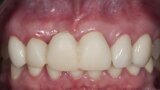

Biomodulacja laserem Nd:YAG z użyciem głowicy Genova®